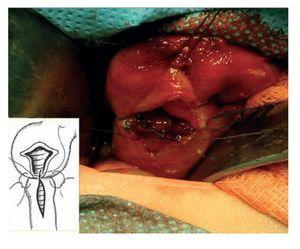

Se incluyeron 41 pacientes, 22 (55%) fueron del género masculino y 18 del género femenino (45%). Treinta y cinco (85%) eran originarios del Distrito Federal y 6 (15%) del Estado de México. El peso promedio al nacimiento fue 2,650 gramos y 24 fueron de término. La manifestación clínica constante fue vómito biliar, ya que se presentó en todos los pacientes. La imagen radiográfica de doble burbuja causada por la dilatación gástrica se observó en 31 pacientes (70.5%) (Imagen 1). La causa de la obstrucción duodenal fue atresia duodenal en 35 casos (86%) y páncreas anular en 6 (14%) (Foto 1). Todos tenían obstrucción posvateriana, 27 de la segunda porción del duodeno (66%) y 14 de la tercera (34%). Ocho (20%) tuvieron trisomía 21.

Imagen 1. Muestra la clásica imagen de "doble burbuja", producida por un nivel hidroaéreo en el estómago y otro en el duodeno. Traduce obstrucción duodenal como síndrome.

Foto 2. Se muestra en vivo y con diagrama en montaje cómo se efectúa la anastomosis duodeno-duodenal en forma de "diamante" u operación de Kimura.